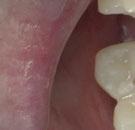

–Implante inmediato en incisivo lateral superior con técnica de «Socket Shield» y acceso vestibular para legrado de la lesión periapical, por el Dr. Ignacio Tormo Jiménez y cols. [106]

–Implantología monofásica, una herramienta más en Rehabilitación oral, por el Dr. Carlos Polis Yanes y cols. [78]